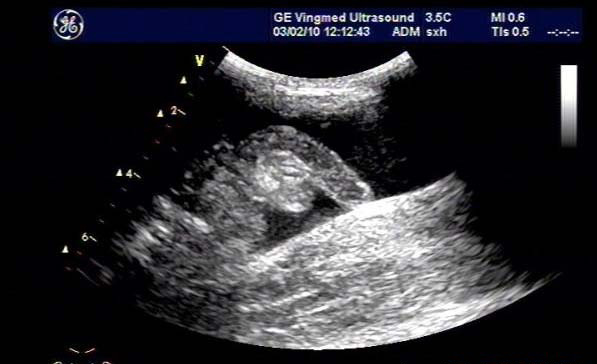

闌尾炎是美國兒童常見的疾病,發(fā)生率持續(xù)增加;雖然CT是最常用來評估疑似闌尾炎患者之癥狀的影像技術(shù),但它與顯著增加放射線暴露有關(guān),而超聲檢查不會有放射線暴露。

研究目標(biāo)是,兒童急性闌尾炎時,使用超聲檢查作為第一種影像檢查方式時,確認是否會增加復(fù)雜性闌尾炎比率與住院天數(shù)(LOS)。